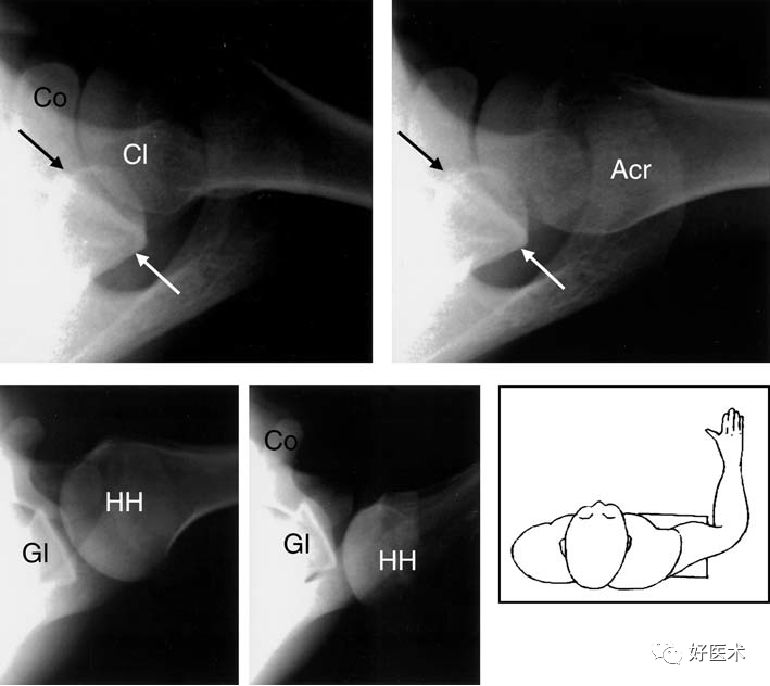

-

对关节盂的上部及后部、肩胛颈的正切显像

同时对盂肱关节位置关系、肩锁关节较精确的评估

肩关节顶斜位

对肱骨头的上后部分、肩关节关节盂前缘的下部很好的成像